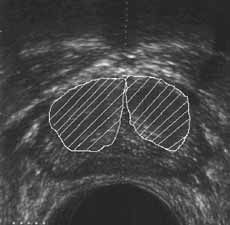

Рис. 11 и 12. (Слева) Переходная зона предстательной железы. (Справа) Периферическая зона предстательной железы.